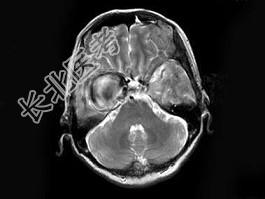

- 单项选择题女,62岁, 头痛数年,头颅MRI检查如图, 最可能的诊断是 ( )

A、脑膜瘤

B、动脉瘤

C、脑出血

D、转移瘤

E、未见异常